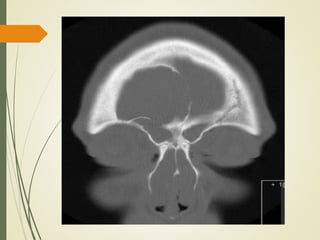

• #43 El diagnóstico se confirmó con tomografía computarizada que muestra una lesión de pared lisa llenar un seno ampliado, con áreas de hueso adelgazado o dehiscentes, por lo general entre el mucocele y la órbita o la fosa craneal anterior.

• #44 Tomografía computarizada coronal que muestra mucocele extradural intracraneal asintomática con colección crónica de moco en paciente con poliposis nasal.